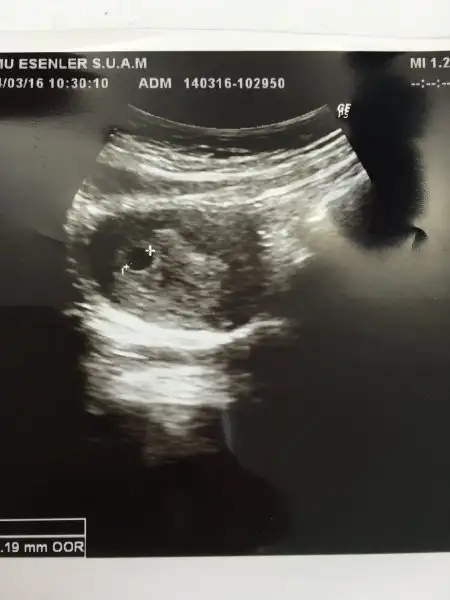

BU DA KESEMİZ DOKTOR ÇOK GÜZEL DEDİ MAŞALLAH HERKES KIZIN OLCAK DİYO NORMALDE KIZ ÇOCUKLARINI PEK SEVİMLİ BULMAM NEDENSE BENİMDE GÖNLÜMDEN GEÇEN KIZ

KIZLAR ÇOK ŞÜKÜR BUGÜN KESEMİZİ KARINDAN ULTRASONLA GÖRDÜK 2 HAFTA SONRA GEL DEDİ DR KALP ATIŞLARI İÇİN ALLAHIM NASIL GÜZEL BİR DUYGU İNŞALLAH HEPİMİZ SAĞLIKLA KUCAĞIMIZA ALIRIZ